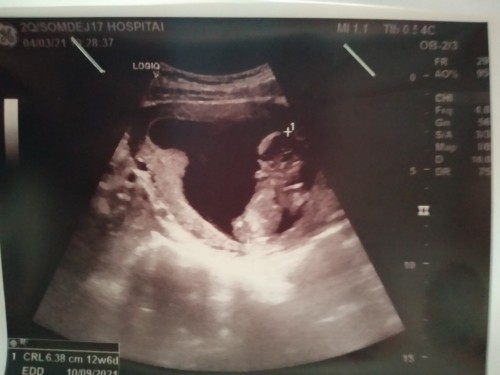

12 w มาครบจ้า